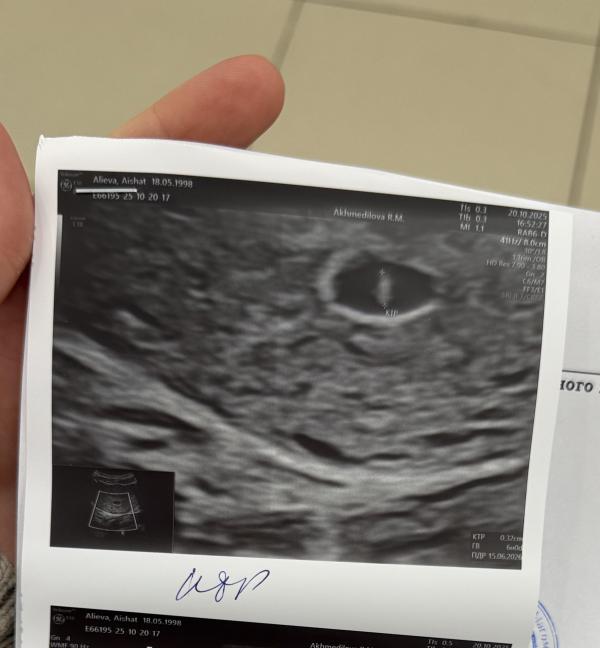

Да, на 5й неделе мне подтвердили маточную беременность, сказали что все хорошо, но сердцебиения пока не было

Ровно в 6 недель четко услышали

На каком сроке уже услышали сердцебиение ?